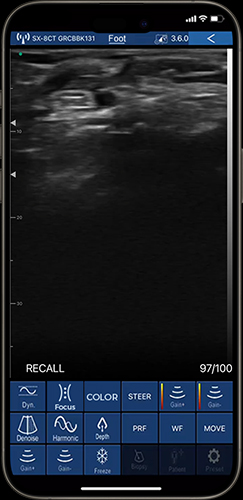

A linear ultrasound probe enables physicians to quickly diagnose musculoskeletal (MSK) injuries in complex environments like sports settings, where injuries such as ACL tears, ankle sprains, Achilles tendon injuries, and tennis elbow are common. Ultrasonic technique particularly allows for real-time visualization and precise targeting for injections and regenerative medicine procedures, ensuring timely and effective treatment. Integral to rehabilitation, MSK ultrasound enables early detection of complications, thus enhancing patient care and recovery outcomes.